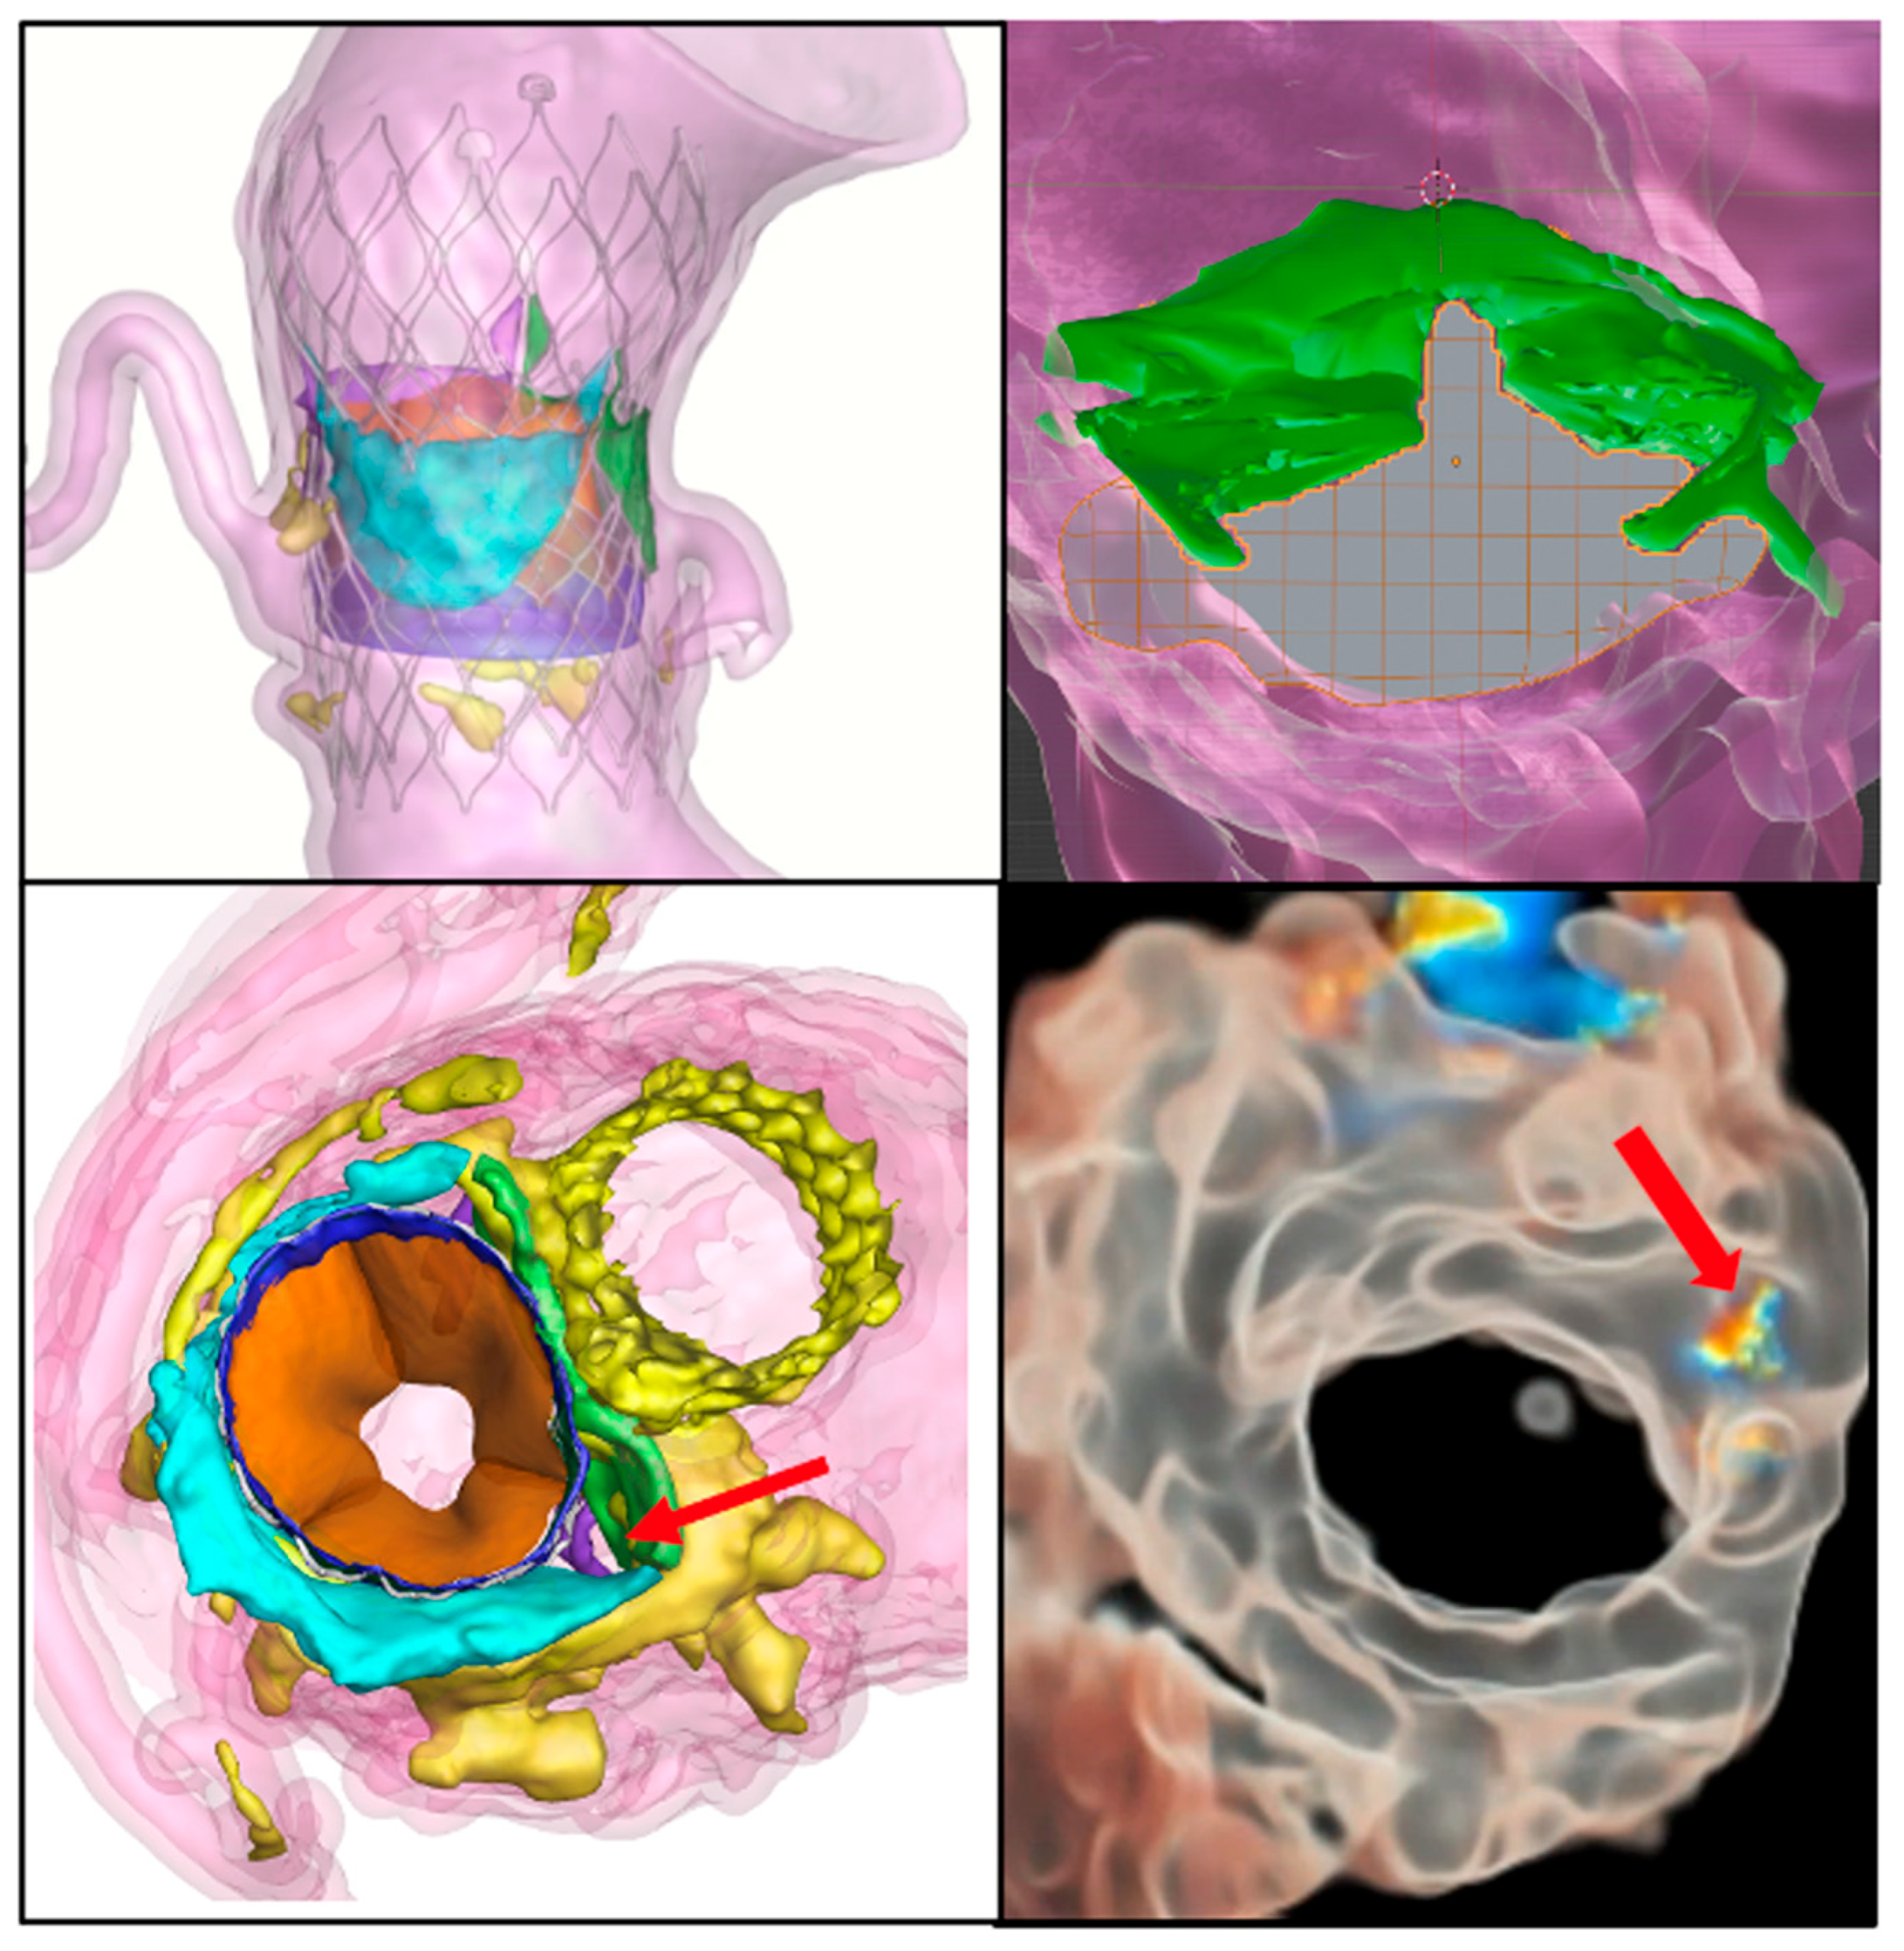

4.1.3. Paravalvular Leak

4.1.4. Percutaneous Alternatives for Coronary Artery Obstruction

4.1.7. TAVI in Bicuspid Aortic Valves